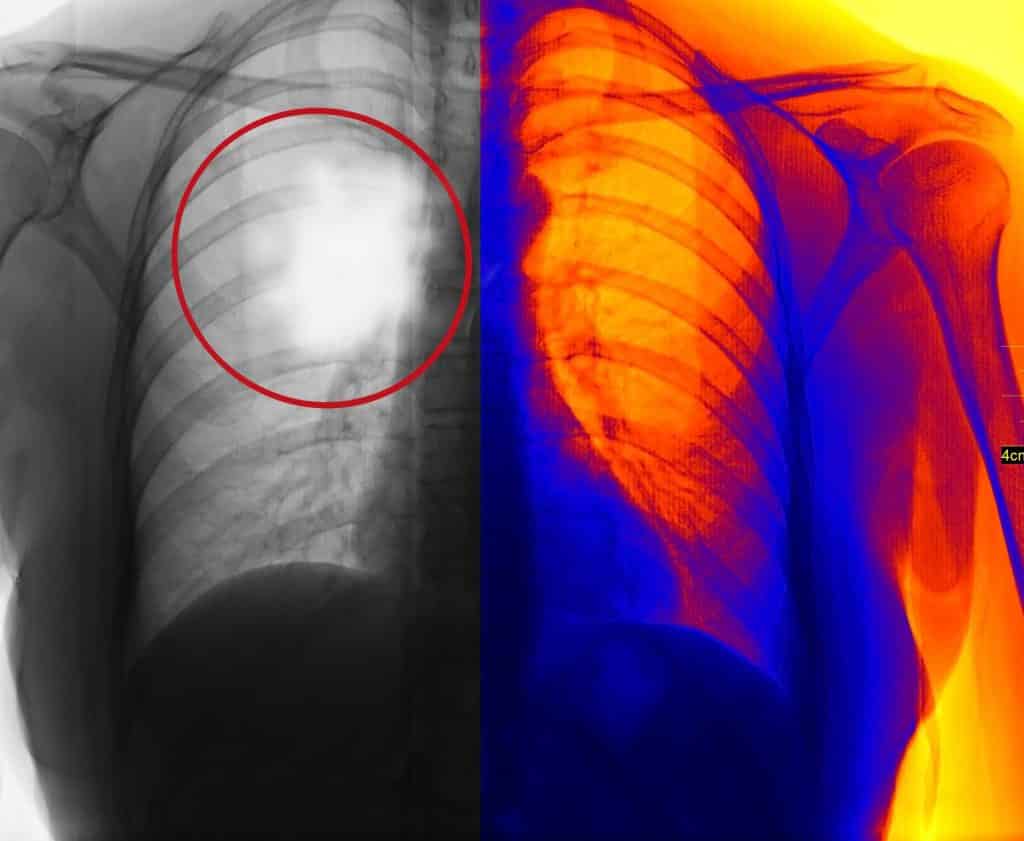

- Imaging Scans. Imaging scans, including X-rays, CT scans, MRIs, and PET scans, help doctors rule out specific conditions. They also help doctors look for areas of abnormal tissue that might be cancerous.